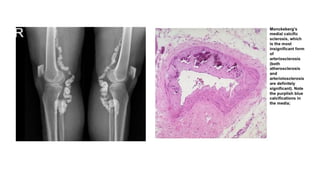

4. MONCKEBERG MEDIAL CALCIFIC SCLEROSIS

• Calcium deposits only in the middle layer without associated inflammatory reaction.

• Affects medium-sized arteries

• Causes vascular stiffening without obstruction of blood flow; intima not involved.

• Not associated with symptoms unless complicated.